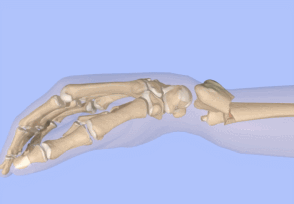

固定的时候推荐的是一个U型石膏,

这样可以有效的减少前臂的旋转并且可以允许一些组织轻微的肿胀。

但是有的时候比较偷懒就常应用一个背侧石膏来防止背侧移位。

5 石膏塑性时候需要进行3点塑性

桡骨远端向掌侧、桡骨近端向背侧、还有一个辅助点在肘部

适当的掌倾、尺偏,不要太过。

注意前臂不要旋前或者旋后,保持中立。

通过这样的三点塑性就可以较好的稳定骨折断端维持较好的力线